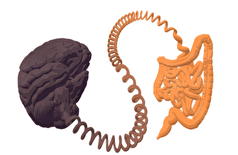

- ارتباط غیرمنتظره بین اوتیسم و سلامت روده!

- Frontiers: روزهداری متناوب بر مغز و روده تأثیر میگذارد